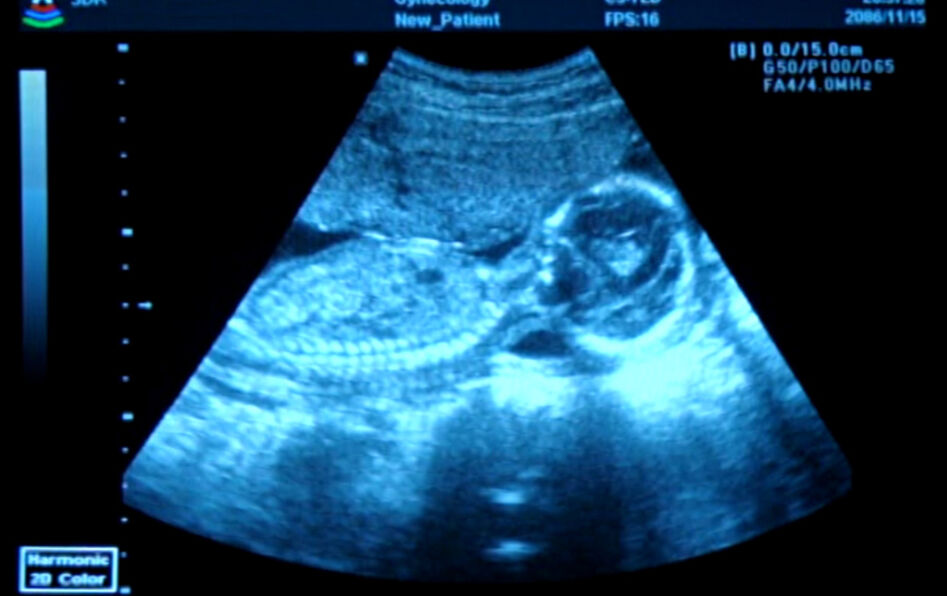

Le fœtus fait-il partie de la famille?

Pour la première foi, la loi permet aux couples d’inscrire un fœtus mort-né à l’état civil. Le fœtus se voit ainsi reconnaître une existence légale. Avancée pour les familles ou menace pour le droit à l’avortement ?

Conférant au fœtus un statut inédit au sein de la famille, ces décrets font écho à une profonde mutation sociétale. Avec les progrès fulgurants de l’imagerie médicale, le processus de personnification de l’enfant en tant qu’être unique et singulier se fait désormais bien avant la naissance. Comment en effet ne pas reconnaître une existence singulière à un fœtus que l’on voit bouger en direct et réagir à certains stimuli ? À cette nouvelle donnée s’ajoute le besoin qu’éprouvent certains parents de faire reconnaître officiellement la douleur qu’ils ressentent à la mort d’un des leurs, fût-il mort-né. Ces décrets soulèvent néanmoins des questions. Parce qu’ils n’ont pas fixé de seuil d’inscription à l’état civil, ils accréditent l’idée que l’on pourrait reconnaître à un embryon (en deçà de dix semaines d’aménorrhée) le statut d’être humain. Et pourraient conduire à remettre en cause de droit à l’avortement…